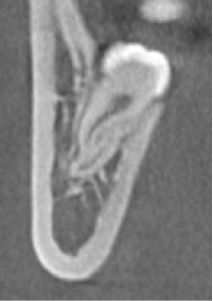

(牙体牙髓医生可以通过CBCT观察需治疗牙的牙根数目及形态)